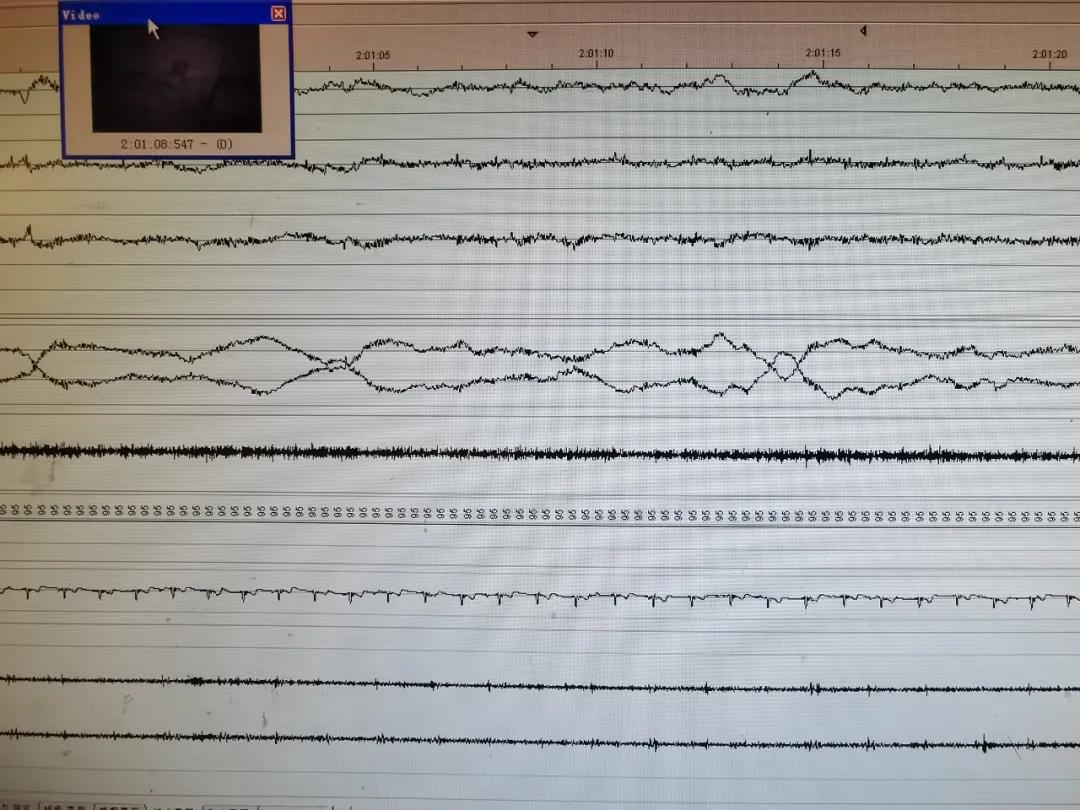

(实时睡眠监测)

近日李女士以白天嗜睡3年,伴心悸2年来我院睡眠诊疗中心就诊。 四川大学华西 春熙医院 四川省第四人民医院呼吸与危重症医学科宇洁主任 接诊后安排李女士在我院睡眠中心行多导睡眠监测,结果提示以阻塞型为主的重度睡眠呼吸暂停综合征,合并重度夜间低氧血症。AHI:77.7/h,最低血氧饱和度75%,最长暂停时间59.5s,血氧低于90%占比48.8%。